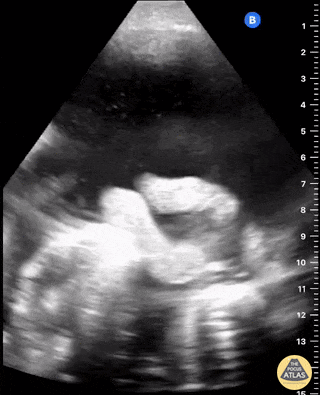

Malignant ascites with plankton sign in woman with metastatic ovarian cancer. Samuel Eglin, MD